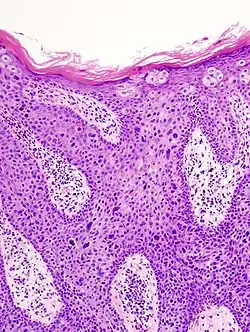

Der Morbus Bowen, auch: Dermatosis praecancerosa Bowen, Erythroplasie de Queyrat (s. u.), Dyskeratosis maligna, ist ein intraepidermales Carcinoma in situ. Dies bedeutet, dass sich die Hautzellen zwar bereits bösartig verändert haben, aber die wichtige Trennschicht Basalmembran noch nicht durchbrochen haben. Erst unterhalb der Basalmembran gibt es in der Haut Blut- und Lymphgefäße. Die bösartig (=maligne) veränderten Zellen des Morbus Bowen können daher nicht metastasieren, da sie keinen Gefäßanschluss haben. Es handelt sich daher beim Morbus Bowen um eine Hautkrebsvorstufe, noch nicht um einen echten Hautkrebs. Nach Monaten bis Jahren kann aus einem Morbus Bowen ein bösartiger Tumor, in diesem Fall ein kutanes Plattenepithelkarzinom (früher Spinaliom, Stachelzellkrebs) entstehen. Ein Plattenepithelkarzinom, das aus einem Morbus Bowen entstanden ist, bezeichnet man als Bowen-Karzinom. Die Veränderungen der DNA der Hautzellen, die zur Entstehung eines Morbus Bowen führen, können durch Sonnenlicht, chemische Stoffe (Arsen) und bestimmte Viren (HPV) ausgelöst werden. Die Erkrankung ist nach John T. Bowen benannt, der sie zuerst beschrieb. Der Morbus Bowen ist eine Erkrankung der zweiten Lebenshälfte und tritt etwas häufiger bei Männern als bei Frauen auf. Neben der Aktinischen Keratose ist er eine weitere wichtige Präkanzerose der Haut.

Die Diagnose wird in der Regel aufgrund feingeweblicher Untersuchung gestellt. In der verbreiterten Epidermis finden sich atypische, zu Einzelverhornung neigende Zellen. Die Basalmembran ist intakt (ansonsten muss man bereits von einem Karzinom ausgehen).